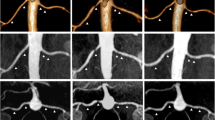

After RDN, in two patients a new renal artery stenosis was observed (lumen reduction in both cases 25–49%) and in one patient there was progression of a pre-existing lumen reduction (from <25% to 50–74%). Two of the three patients with vascular changes were treated with the Symplicity™ catheter and one with the EnligHTN™ multi-electrode system.

To assess the possible relationship between vascular changes and the radiofrequency ablations, we analysed the DSA images performed during RDN. In only one of the three patients with vascular changes after RDN we could conclude that ablations were applied near the location where on the follow-up MRA a new stenosis was observed (Fig. 1). Furthermore, we concluded that findings on the pre-procedural MRA corresponded to the DSA images.

Based on the evaluation of the procedural angiographies, we concluded that only in one patient the newly observed stenosis was located in an ablated area. A relationship with the procedure could therefore not be excluded. In the other two patients, there was no reason to believe that the new or progressed lumen reduction after RDN may have been a result of the ablations (very proximal stenosis and more distally ablated). The natural history of renal vascular anomalies within 1 year in hypertensive patients who had no stenosis at baseline is not often investigated. In 1998, Caps and co-workers reported a cumulative incidence of progression to ≥60% stenosis of at least 5% after 1 year in patients who were initially wrongly suspected of having atherosclerotic renal artery stenosis (investigated by duplex ultrasonography) [32]. The cumulative incidence of progression in patients with pre-existing stenosis was almost five times higher. Two other studies showed that in a population of resistant hypertensive patients with relatively high vascular morbidity, occurrence or progression of renal artery atherosclerosis is very likely [33, 34]. For a correct interpretation of the currently presented results, a comparison with (randomized) control patients and differentiation between atherosclerosis and other causes of renal artery stenosis would be useful. However, this differentiation is radiologically challenging.